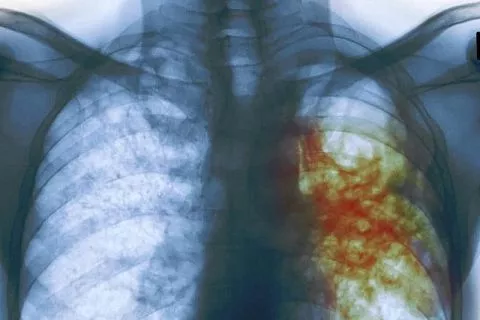

Больной от прохождения лечения уклонялся и отказывался от госпитализации. Фото: zdorovie-legkie.ru

Как сообщили в пресс-службе краевой прокуратуры, в начале 2019 года мужчина был поставлен на диспансерный учет у фтизиатра с открытой формой туберкулеза. При этом больной от прохождения лечения уклонялся и отказывался от госпитализации, что создавало опасность для других людей.